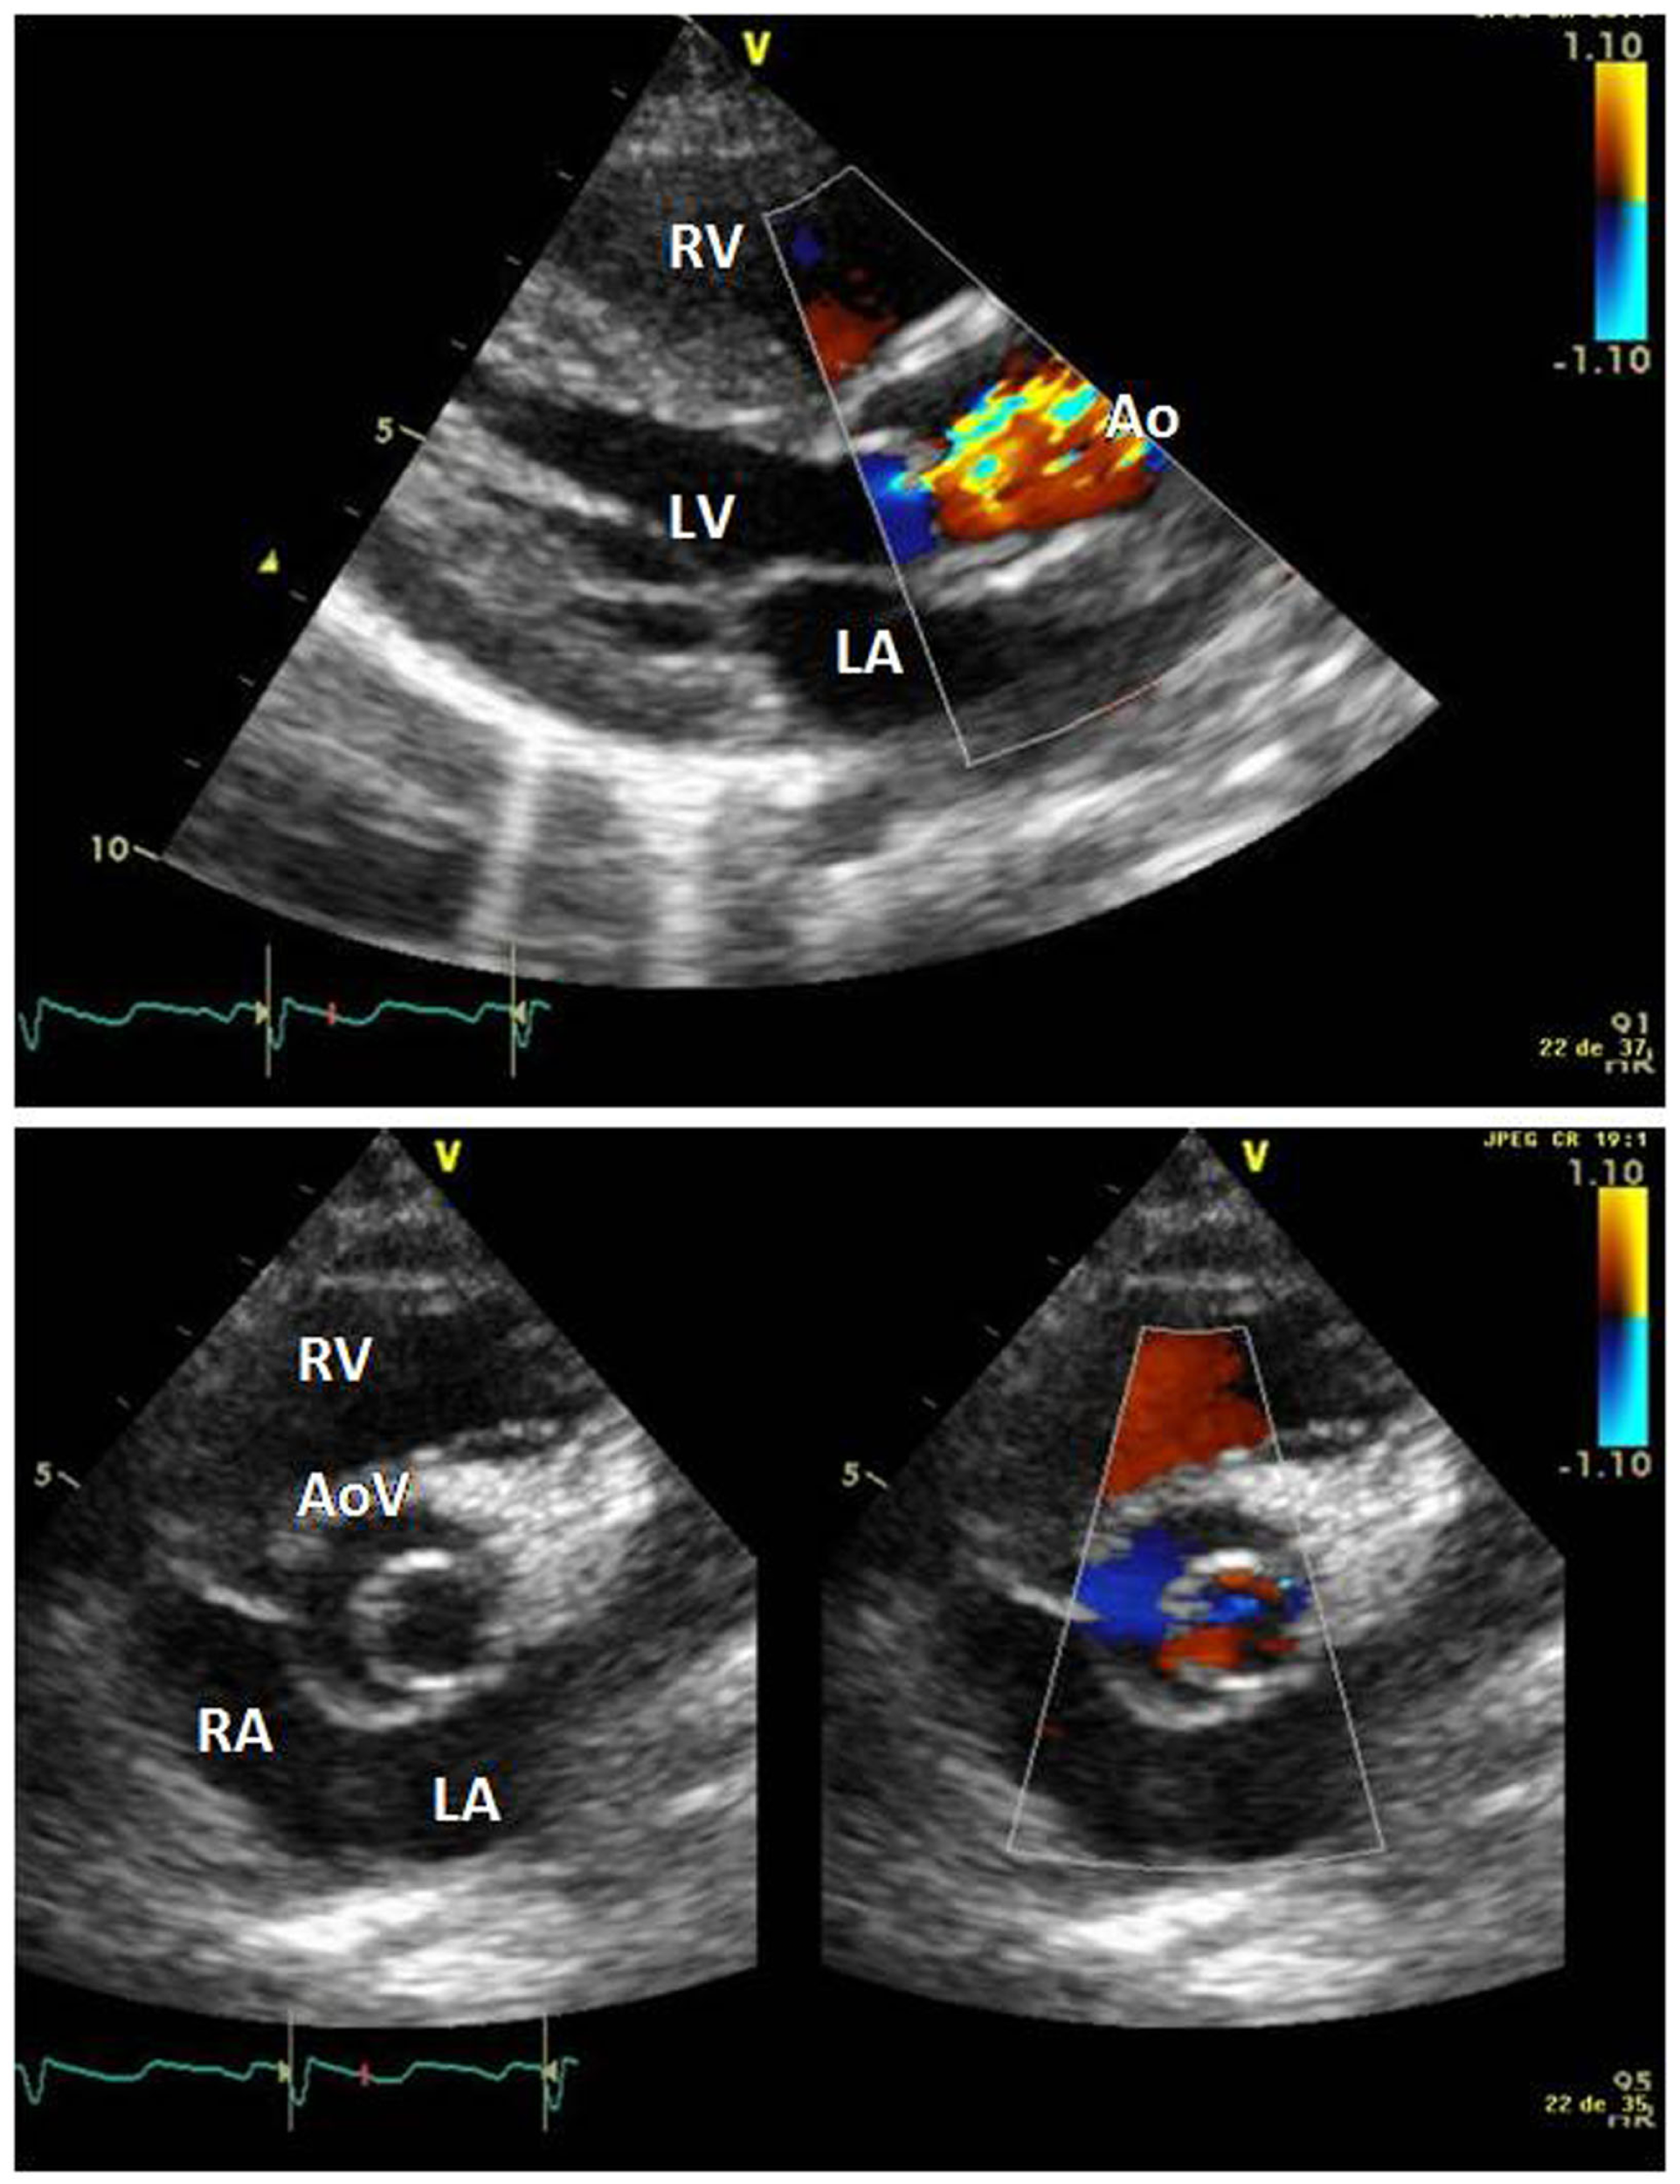

The electrocardiogram showed sinus rhythm with signs of left auricular hypertrophy, but no ventricular hypertrophy. The chest radiography (Figure 1) showed mild cardiomegaly (ICT 0.64) and an absent aortic knob, compatible with the diagnosis of coarctation. The echocardiography showed a bicuspid aortic valve (Figure 2) with severe stenosis (peak systolic gradient of 60 mmHg and mean of 30 mmHg), left ventricular hypertrophy (Z-score +3.3), preserved systolic and diastolic function (mitral E/A ratio 1.6; mitral A deceleration time 0.10 s, E/E′ 22 secondary to increased left heart filling pressure), and tortuous aortic arch with narrowing and acceleration of flow at the aortic isthmus (Figure 3). CMR with angiography showed absence of continuity between the ascending aorta distal to the left subclavian artery (Type 1) and the descending aorta, extending over 5 mm. There was a bend in the arch and diverticulum on either side of the zone of discontinuity, making the diagnosis of atresia rather than interruption of the aortic arch. There was no patent ductus arteriosus (PDA), no associated endofibroelastosis and the descending aorta was fed exclusively by massive systemic collateral circulation (Figures 4–6).

Figure 2

Long axis parasternal view showing doming of the aortic valve, aliaising of flow secondary to stenosis, and left ventricular hypertrophy. Short axis view showing bicuspid aortic valve. Abbreviations: AoV, aortic valve; LA, left atrium; LV, left ventricle; RV, right ventricle.